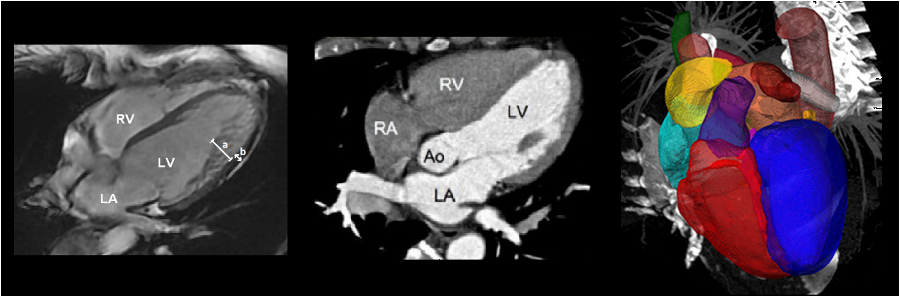

One of the often used datasets for unsupervised domain adaptation for image segmentation in the medical domain is the MM-WHS dataset [11] of whole heart CT and MRI scans. In the following image, an example from that dataset is shown. The segmentation classes are different parts of the heart that should be distinguished.

Example from MM-WHS dataset; source: [11]